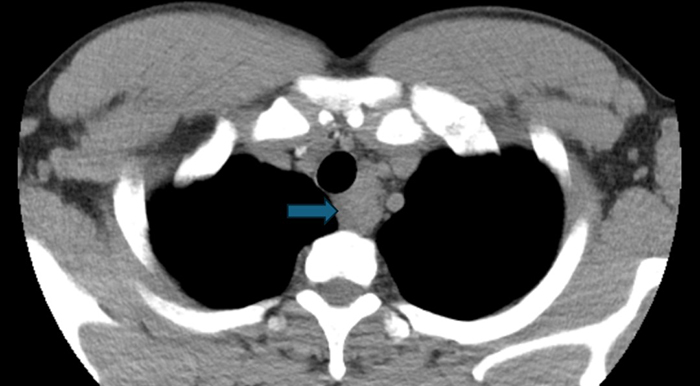

一个月前,我收到胸外科同事递来的一张内镜检查申请单:36岁男性,发现“纵隔肿物”。这类患者在我院并不少见,但每一次,我都如履薄冰。打开他的胸部CT,我仔细观察肿物与食管、气管的位置关系——距离够近,路径可行。我回复了一个字:“能。”——我们可以通过超声内镜穿刺活检,一探究竟。

胸部CT图片(纵隔肿物位于箭头所指位置)